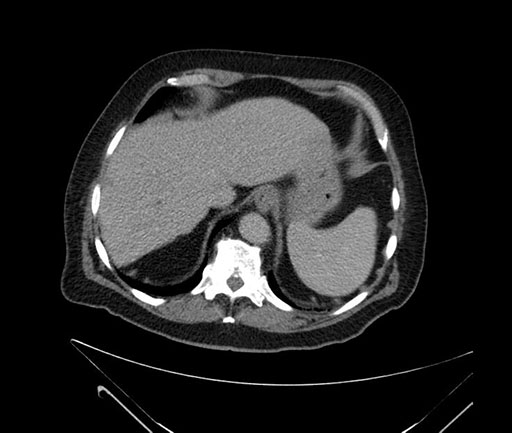

Axial - 3 months prior